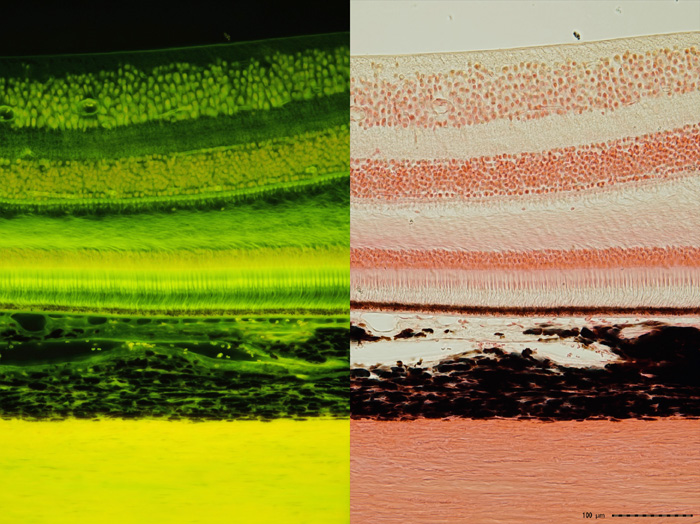

サル眼球壁

左490nmLED 対物: x20 撮像: x2.5 電流: 0.4A ISO:400 露出0.4 sec

右透過照明